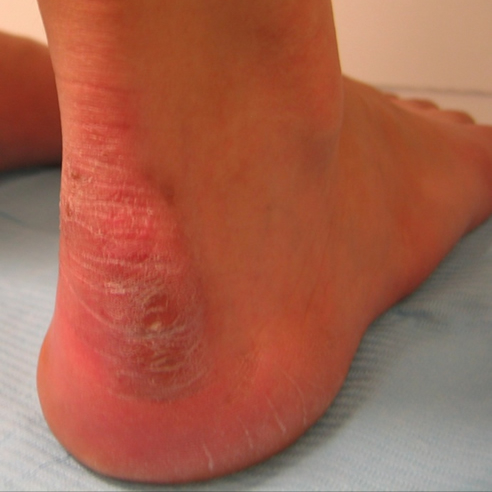

Exóstosis retrocalcánea (Deformidad de Haglund)